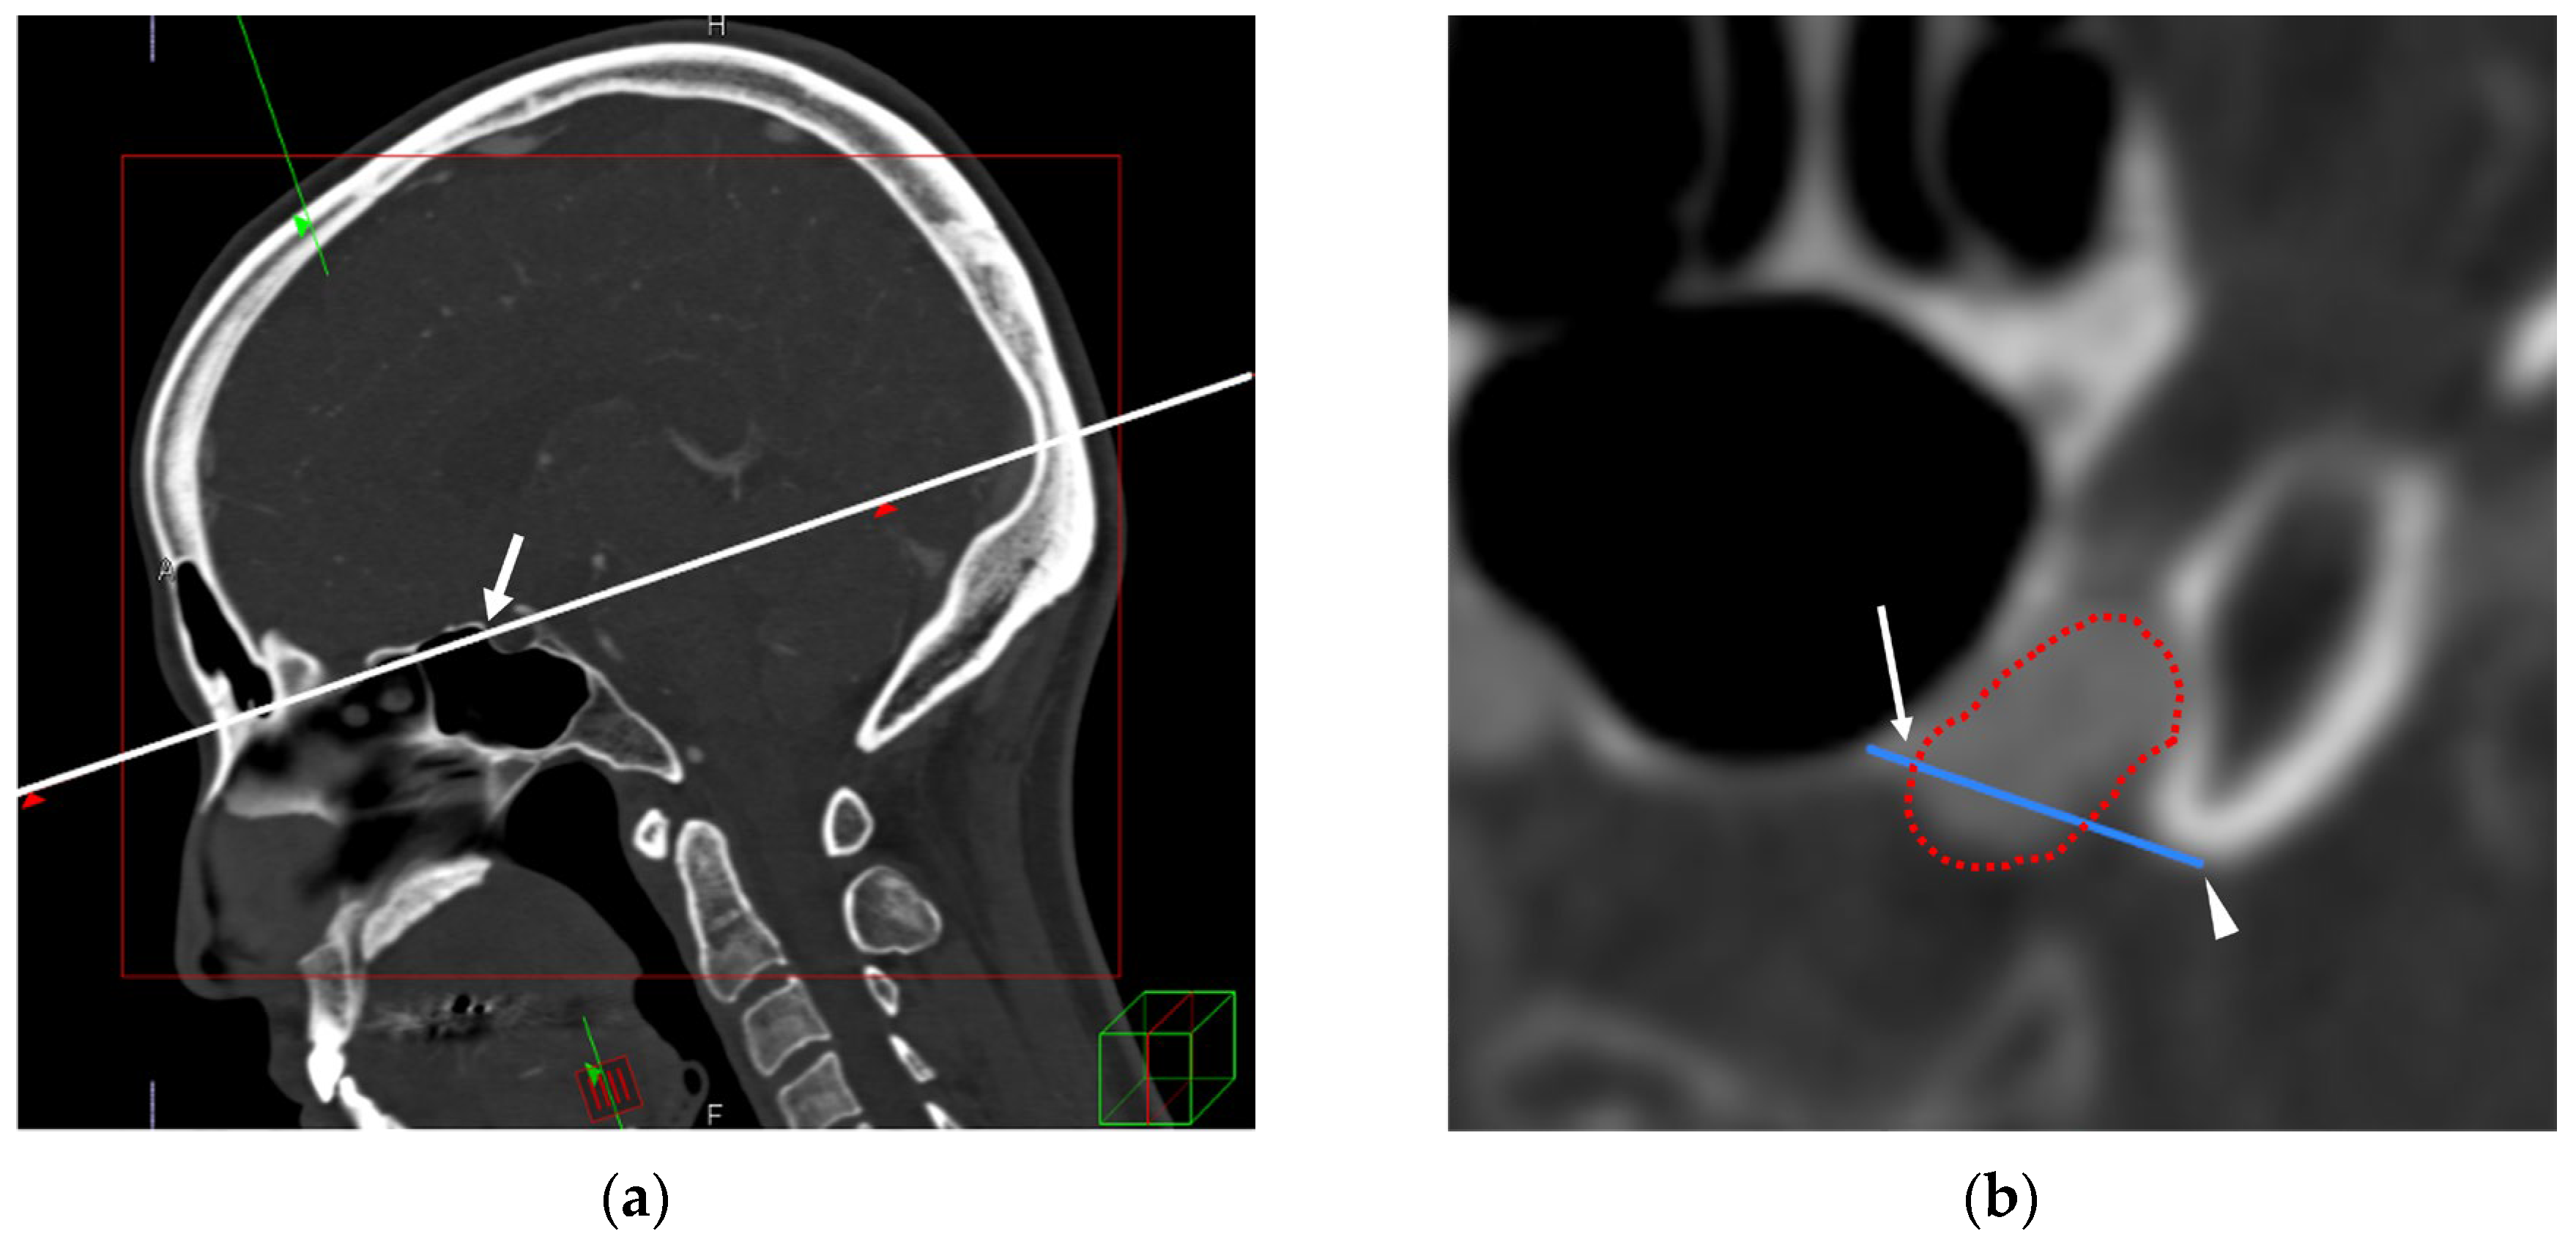

2.4. TS–ACP Line Method

2.5. Image Analysis